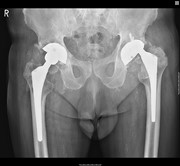

Metallosis following full thickness wear in total hip arthroplasty

Nicholas Birkett and others

Journal of Surgical Case Reports, Volume 2015, Issue 9, September 2015, rjv122, https://doi.org/10.1093/jscr/rjv122